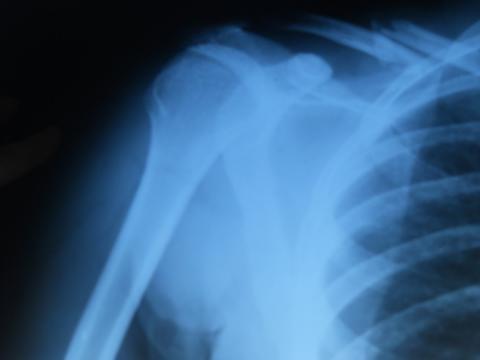

Pro větší náhled klikněte na obrázek

Dobrý deň,chcela by som sa spytat na Vas nazor ohladne zlomeniny klucnej kosti mojho priatela.Úraz sa mu stal v rumunsku 15.9.2011 kde v nemocnici boli za operaciu,ale chceli sme ho radsej previezt naspät domov na Slovensko. Tak dalsi den sme sa dostali na urgent kde mu kost prehmatali a nejak "napravili" ale nam sa to vobec nepozdava.Ma to spevnene popruhom stella a stazuje sa ze citi pri pohybe ako sa mu kosticky hybu. Takto ma cakat do 21.9. na dalsiu kontrolu. Vôbec niesme spokojni s takymto postupom, logika nas vedie k tomu,ze preco by sa mali tie kosti zrastat tak ako vidite na snimku (ako nam odporucili v nemenovanej nemocnici) a nie chirurgickym zakrokom,kde by mu mohli kosticky napravit do povodnej polohy pouzitim drotov. Prosim aky mate na to nazor?

Dobrý den,záleží na posuzení stavu ošetřujícím lékařem. V případě, že nejste spokojená, tak to řekněte přímo lékaři. Je možné si vyžádat na léčbu další názor jiného chirurga. Pokud s léčbou nesouhlasíte je nutné to oznámit přímo lékaři. Tady v poradně s tím nic neuděláme. Snímek je proveden před fixací, tudíž takto to určitě srůst nemá. Doporučuji zmínit Vaše obavy a připomínky k léčbě na prohlídce přip. dříve.